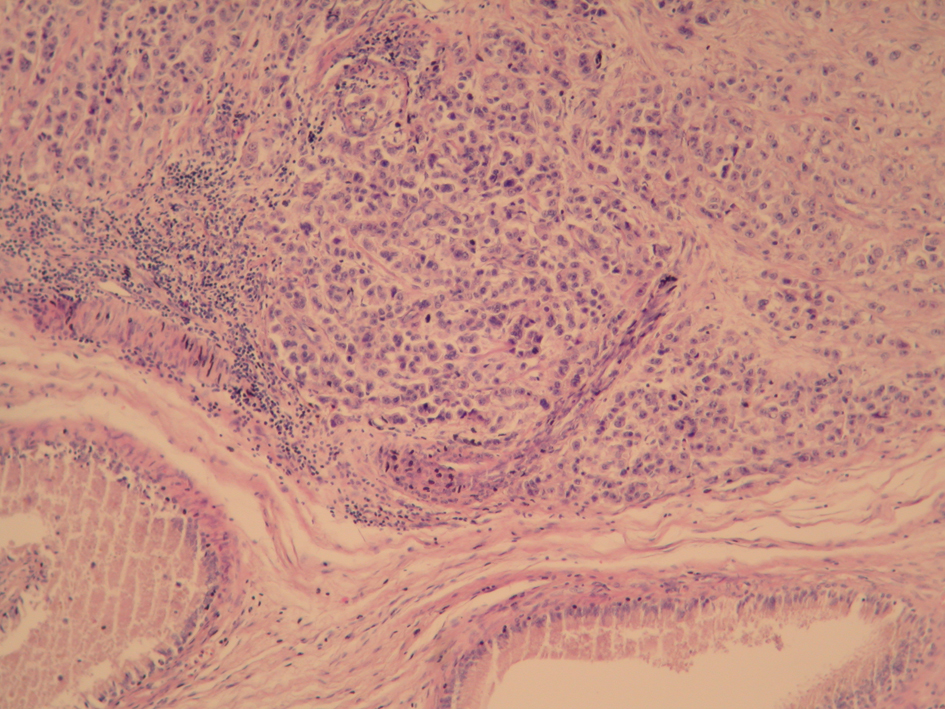

A 68-year-old male presented to our outpatient department with painful, palpable mass in his left testis that was gradually progressive for 2 months. On the physical examination a hard palpable mass of size 5 x 4 cm mass cm was detected in the a testicular enlargement on the left hemiscrotum and lymph nodes were not in the inguinal region. The scrotum was normal except for an apparent enlarged. He had no history of previous surgery or trauma to the testis. The patient is unknown any exposure to asbestos in the past. The laboratory examinations was normal in complete blood count and renal and liver functions. Alpha fetoprotein was 3.07 ng/mL (normal < 20 ng/mL) and the beta human chorionic gonadotropin level was 1.20 mIU/mL (normal < 5 mIU/mL). In the ultrasound examination it was observed that the left testis was enlarged 5 cms showing diffusely heterogenous echo-texture and irregular nodular surface with irregular hypoechoic thickening of the scrotal. Computed tomography performing for staging showed a nodular mass in left testis and he had not distatnt metastasis. The patient was undergone left radical orchiectomy for treatment and diagnosis aims. Macroscopically, the left orchiectomized specimen, 4 x 5 cm in size, was composed of the testis with a paratesticular tumor mass arising from the tunica vaginalis. Microscopically, in the testicular tissue, uniform cuboidal shapeda typical cells showed parenchimal infiltration (Fig. 1) and strong positivity with mesothelin (Fig. 2) that suggestive of the diagnosis of epithelial mesothelioma. With all of these findings, localizated stage Malign Mesothelioma of testis was diagnosed to the patient. The patient was managed radiotherapy to prevent from recurrence. The patient is alive for two years without recurrence.

![]() Click for large image | Figure 1. Uniform cuboidal shaped atypical tumoral cells infiltrating the testis tissue (H and E stain, x100). |